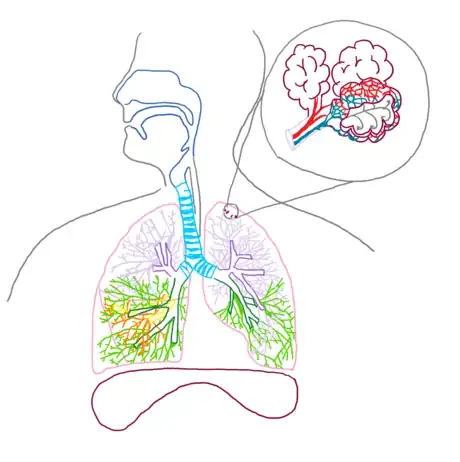

6Detail the alveoli. Redraw a segment of the bronchioles and attached alveoli in the microscope box. The bulbous “grape” like structures of the alveoli are called alveolar sacs, and the segment of branching immediately before the alveoli are called alveolar ducts.

- In addition to these structures, draw an overlay of the pulmonary artery (red) and pulmonary vein (blue) leading into the arteriole and venule capillary system.

7Label your completed diagram. Draw lines away from each structure to an open space using a ruler or straight edge. Clearly label each structure or region correctly. For more complex drawings, it is sometimes beneficial to label structures numerically and then provide an organized key.